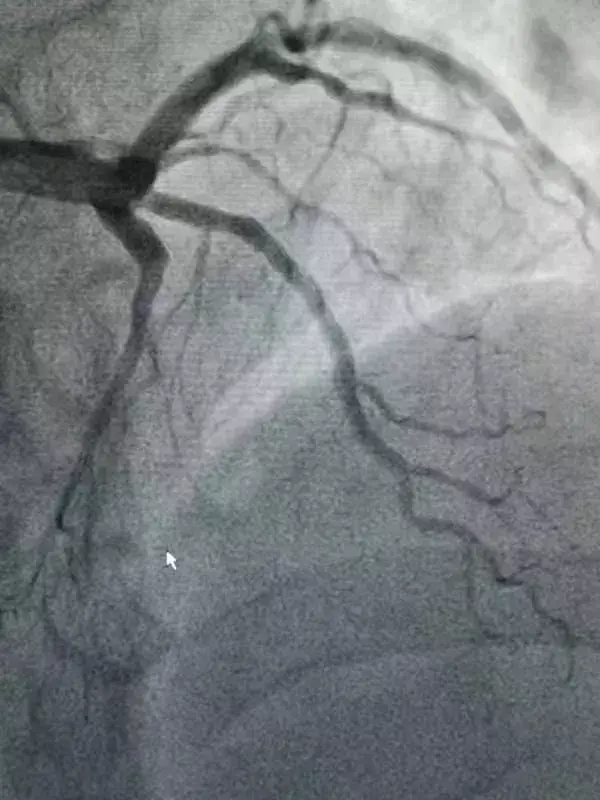

随着救护车急促的铃响,该患者抵达我院急诊科,刘秀敏副主任医师已提前在急诊科等候,在核对患者身份信息无误后,立即对该患者复采核酸,并在电话沟通中得知患者于当地核酸抗体检测为阴性后,立即将病人送至手术室。为确保安全,准备了隔离衣、N95口罩、面屏灯防护措施,心内一病区手术团队顺利为该患者实施了冠脉介入手术,及时开通闭塞的前降支病变。

术前